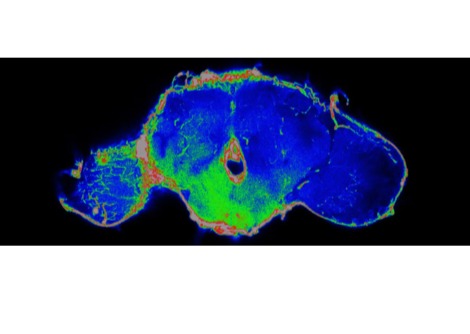

في عام 2023، حاول باحثون في جامعة بنسلفانيا استخدام كبد خنزير معدل وراثيًا كجهاز احتياطي، حيث تم توصيل العضو خارجيًا بشخص توفي مؤخرًا. وتمكن الفريق من تدوير دم الشخص من خلال كبد الخنزير، وهي خطوة نحو استخدام العضو للقيام مؤقتًا بمهام الكبد لدى مرضى فشل الكبد. وفي الحالة الجديدة، أدخل الجراحون الكبد إلى داخل الجسم. بدأ الفريق بخنزير باما مصغر، حُذفت منه بعض جينات الخنزير، وأُضيفت إليه جينات بشرية. تلعب هذه الجينات دورًا في رفض عملية الزرع؛ وكان الهدف من هذه التعديلات تقليل احتمالية فشل عملية الزرع.

وضع الجراحون الكبد المعدّل داخل جسم المتلقي، ووصلوه بأوعيته الدموية، ثم راقبوه لمدة 10 أيام. احتفظ كبد الخنزير بوظائفه، وتدفق الدم بسلاسة، ولم يلحظ فريق وانغ تراكمًا للخلايا الالتهابية، وهو ما يُشير إلى تقبّل المتلقي البشري لعملية الزرع. بعد التجربة، أُعيد جثمان المتلقي إلى عائلته.